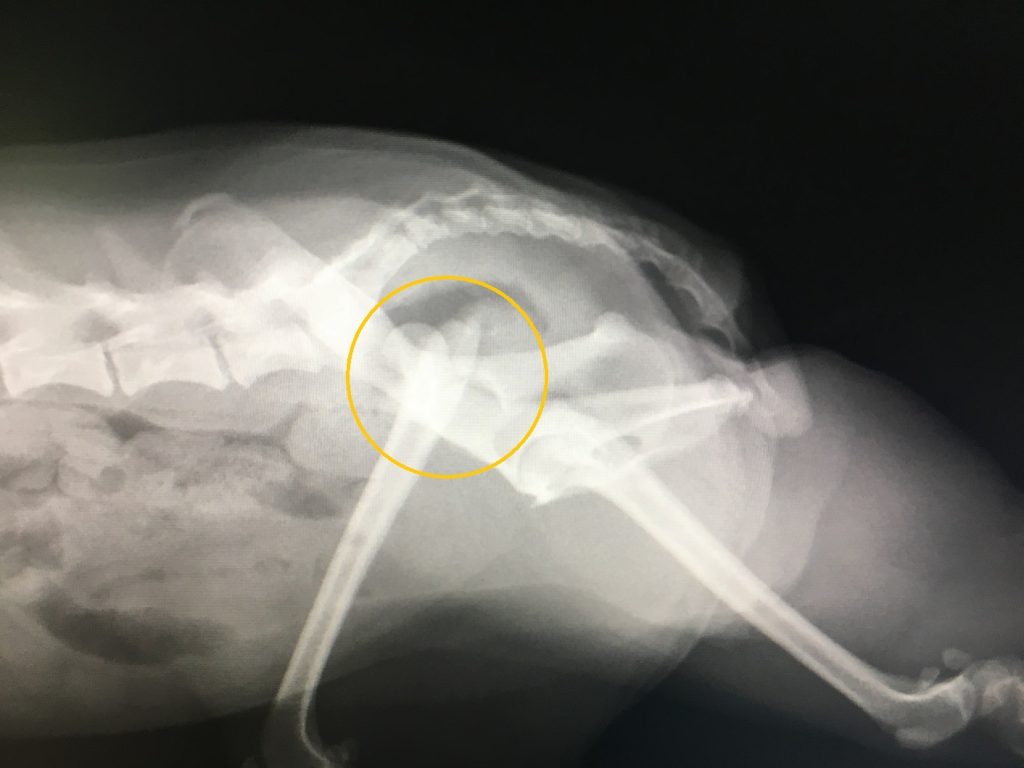

来院時の触診では股関節部に激しい痛みが認められ、レントゲン検査を行ったところ、左後肢の股関節脱臼が確認されました。

股関節脱臼は、大腿骨(太ももの骨)の骨頭が骨盤の寛骨臼から外れてしまった状態になることです。外傷性の股関節脱臼は、交通事故や落下などによって起こります。